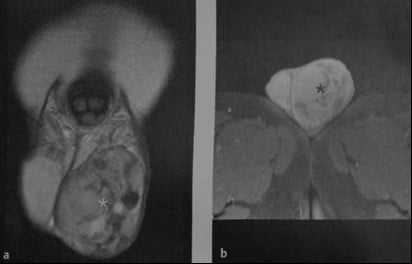

Нормальные яички. МРТ: (а) Аксиальное Т2-взвешенное изображение. Нормальная интенсивность сигнала от яичек; (b) Сагиттальное Т1 -взвешенное изображение после внутривенного введения контрастного вещества. Сигнал средней интенсивности от яичка. Нормальный хвост придатка (стрелка).

Что покажет МРТ при нормальной мошонке

- гомогенный сигнал средней интенсивности на Т1-взвешенном изображении

- Высокая интенсивность сигнала на Т2-взвешенном изображении

- Гипоинтенсивная перегородка идет радиально от капсулы к средостению яичка

- Белочная оболочка: тонкая линия с низкой интенсивностью сигнала

- изоинтенсивный по сравнению с яичками на Т1- взвешенном, гипоинтенсивный на Т2-взвешенном изображении

- более выраженное контрастное усиление по сравнению с яичками.